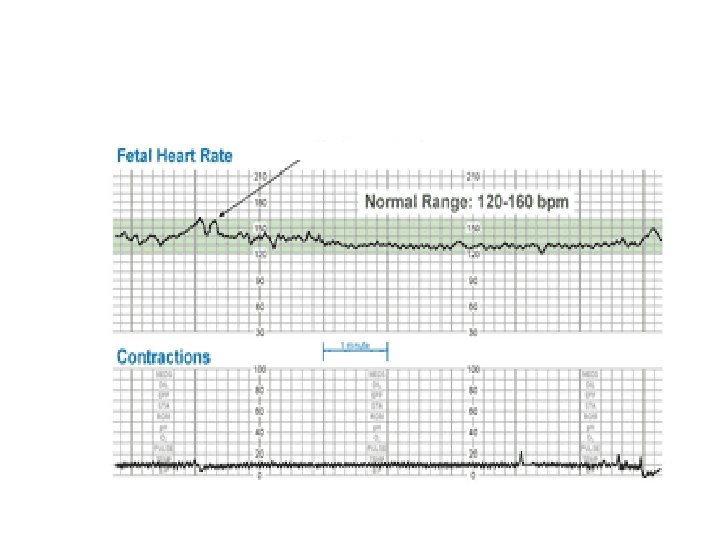

Baseline Fetal Heart Rate The baseline FHR is the heart rate during a 10 minute segment rounded to the nearest 5 beat per minute increment excluding periods of marked FHR variability, periodic or episodic changes, and segments of baseline that differ by more than 25 beats per minute. • The minimum baseline duration must be at least 2 minutes. • If minimum baseline duration is < 2 minutes then the baseline is indeterminate. • Normal baseline = 110 -160 bpm

Category I All of the following criteria must be present. Tracings meeting these criteria are predictive of normal fetal acidbase balance at the time of observation. Baseline rate: 110 to 160 bpm Moderate baseline FHR variability No late or variable decelerations Early decelerations may be present or absent Accelerations may be present or absent